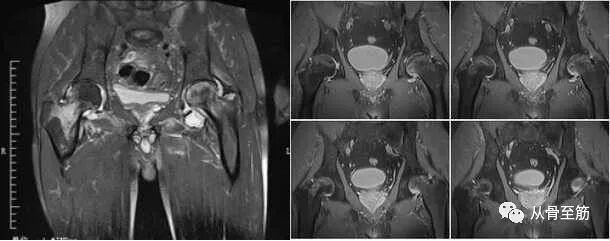

有明确原因的骨髓水肿当然很好鉴别。有一种叫股骨头骨髓水肿综合征的情况有时难以区分,是一种病因未明、以髋关节骨质疏松为特征的自限性疾病。中年发病,男性多于女性,多为单侧受累。临床变现为无明显诱因的进行性髋部疼痛、跛行、髋关节旋转活动受限。核磁共振表现为广泛均匀的骨髓水肿,信号改变可达股骨颈和大转子。自然病程半年至1年,临床症状消失,核磁共振可完全恢复至正常。

股骨头坏死是因为缺血引起,最终出现股骨头塌陷和髋关节功能障碍的一种慢性疾病,在核磁上也可以出现骨髓水肿。核磁是目前诊断早期股骨头坏死较为敏感的检查。MRI表现是坏死与水肿两种征象的结合。?

股骨头骨髓水肿综合症与股骨头坏死的预后和治疗完全不同。股骨头坏死引起的骨髓水肿,在磁共振上有典型的双边征改变,即股骨头软骨下区内出现带状或环状低信号带特征性改变,范围局限于病灶周围。股骨头骨髓水肿综合征的表现为较为均匀的水肿,可波及股骨颈和大转子。